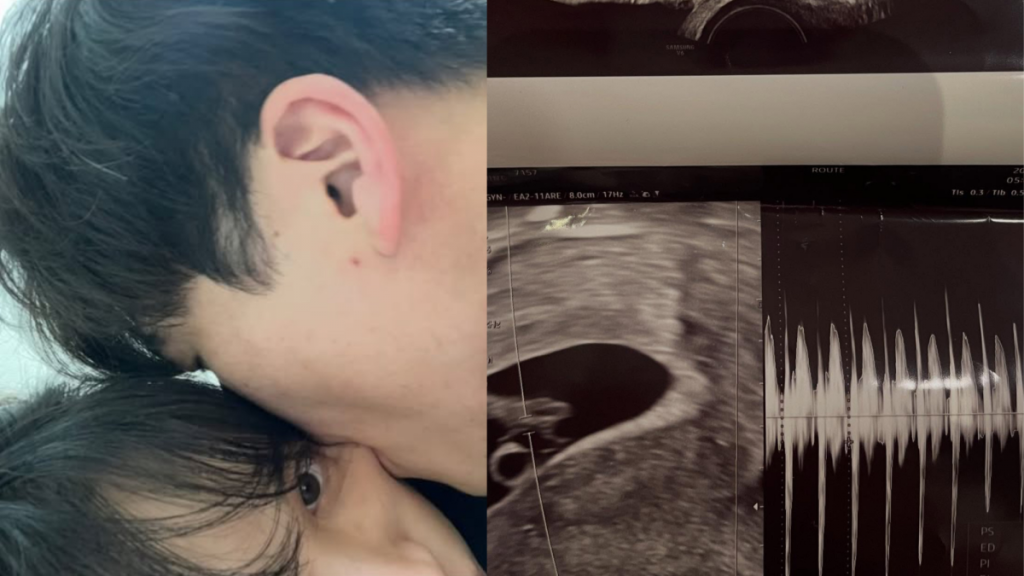

서민재는 2일 SNS 계정에 “아빠 된 거 축하해”라는 글과 함께 태아 초음파 사진을 공개했다.